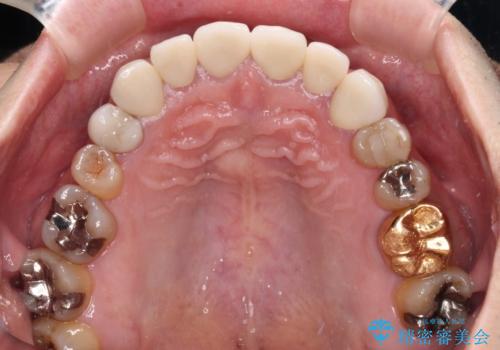

長年前歯の色の違いに悩んでいらっしゃったようですが、仮歯に変えた時点で統一感のある白さとなり喜んで頂きました。

わずか1ヶ月の間にとても自然な仕上がりのセラミッククラウンが装着され、患者様には大変満足していただきました。